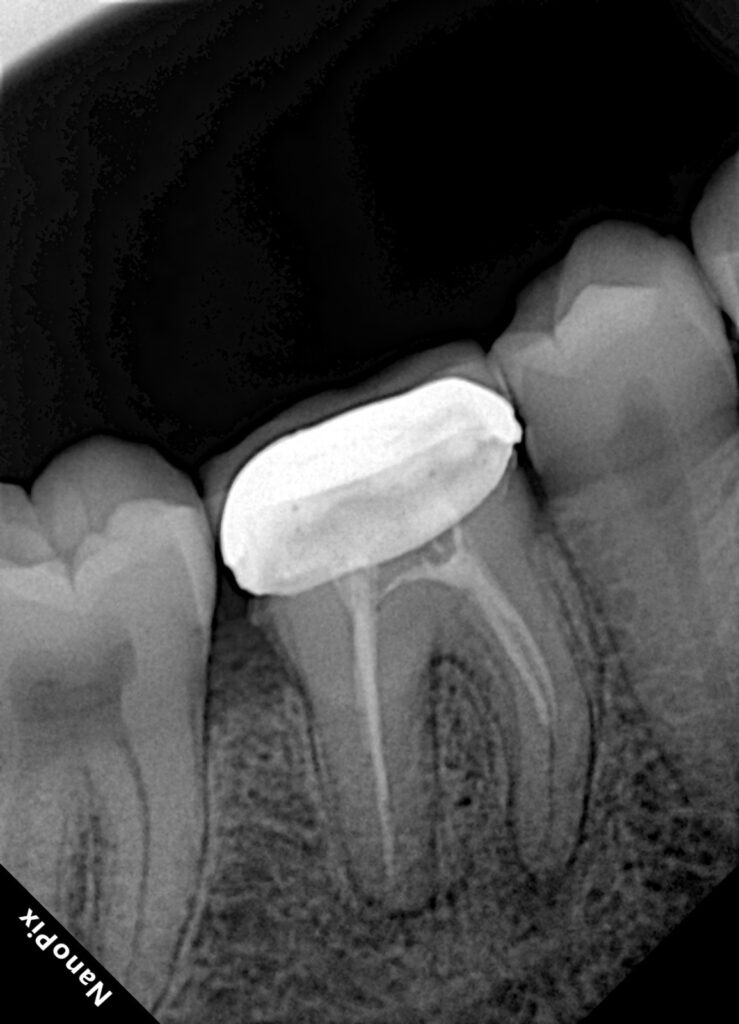

Non-Surgical Re-Endodontic Management of a Mandibular Molar Through an Existing PFM Crown: Step-by-Step Identification and Negotiation of the Middle Mesial Anatomy

Persistent apical disease following root canal treatment is most commonly associated with residual intraradicular infection, often due to missed or inadequately disinfected canal anatomy. Mandibular molars present a high degree of anatomical complexity, particularly within the mesial root, where the middle mesial (MM) canal system may exist as an independent canal, a confluent pathway, or an isthmus.

This case report describes a conservative, non-surgical retreatment of a mandibular molar performed through an existing porcelain-fused-to-metal (PFM) crown, with specific emphasis on systematic identification, troughing, and negotiation of the middle mesial anatomy under strict rubber dam isolation and magnification. The article outlines a step-by-step, clinically reproducible protocol focused on biological principles, controlled ultrasonics, conservative shaping, and effective disinfection.

The tooth presented with previous root canal treatment and persistent periapical pathology. An existing PFM crown was clinically intact with acceptable margins and allowed predictable rubber dam isolation. Considering the risk of crown removal and the ability to achieve an adequate coronal seal, a through-the-crown retreatment approach was selected.

Pre-operative radiographic assessment suggested incomplete debridement of the mesial root, raising suspicion of missed mesial anatomy.

3. Pulp Chamber Refinement and Anatomical Mapping

After removal of restorative materials, the pulp chamber floor was cleaned and inspected under magnification. The MB and ML canal orifices were identified first. Attention was then directed to the developmental groove connecting the mesial canals, which was carefully examined for color changes, catch points, and anatomical clues.

4. Ultrasonic Troughing of the Middle Mesial Groove

A fine ultrasonic tip was used to trough the mesial developmental groove at low to moderate power. Troughing was performed incrementally with frequent irrigation and reassessment.

5. Negotiation of the Middle Mesial Anatomy

Upon identifying a reproducible catch point, a pre-curved size 6 and 8 stainless steel hand file was introduced using EDTA as a lubricant. Gentle watch-winding and picking motions allowed progressive negotiation.

The pathway demonstrated consistent re-entry and apical progression, confirming a functional middle mesial anatomy rather than a superficial isthmus alone.

8. Obturation

The root canal system was obturated using a technique appropriate for complex anatomy, ensuring sealing of the MB, ML, and middle mesial components. Particular care was taken to achieve homogenous filling of the mesial root.

Middle mesial anatomy plays a significant role in the failure of mandibular molar endodontic treatment. Whether present as a true canal or a confluent isthmus, this region harbors bacteria that cannot be eliminated without direct negotiation and irrigation.